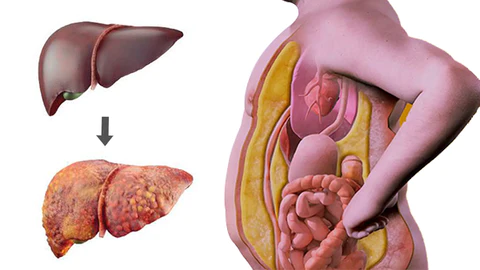

AAFQ™ Polygonum Multiflorum and Ginseng Extract Herbal Spray is specifically formulated to address conditions such as fatty liver, alcoholic hepatitis, liver fibrosis, obesity, insomnia, cirrhosis, hair loss, jaundice, gallbladder disease, and liver dysfunction. Our formula is designed to provide powerful liver support through sublingual absorption, activating liver cell regeneration, repairing the liver, enhancing detoxification capabilities, reducing inflammation, and decreasing visceral fat. By using our spray, you can expect increased energy and vitality within 8 weeks, helping you regain robust liver detoxification function.

AAFQ™ Polygonum Multiflorum and Ginseng Extract Herbal Spray is specifically formulated to address conditions such as fatty liver, alcoholic hepatitis, liver fibrosis, obesity, insomnia, cirrhosis, hair loss, jaundice, gallbladder disease, and liver dysfunction. Our formula is designed to provide powerful liver support through sublingual absorption, activating liver cell regeneration, repairing the liver, enhancing detoxification capabilities, reducing inflammation, and decreasing visceral fat. By using our spray, you can expect increased energy and vitality within 8 weeks, helping you regain robust liver detoxification function.

AAFQ™ Polygonum Multiflorum and Ginseng Extract Herbal Spray” is designed for sublingual absorption, allowing its ingredients to act on the liver through the bloodstream. It stimulates rapid regeneration of liver cells and enhances detoxification effects, providing liver support within one day and promoting liver health restoration. AAFQ™ research team has pioneered an efficient extraction technique that combines active components from various herbs, enabling you to achieve a healthy liver within four weeks.